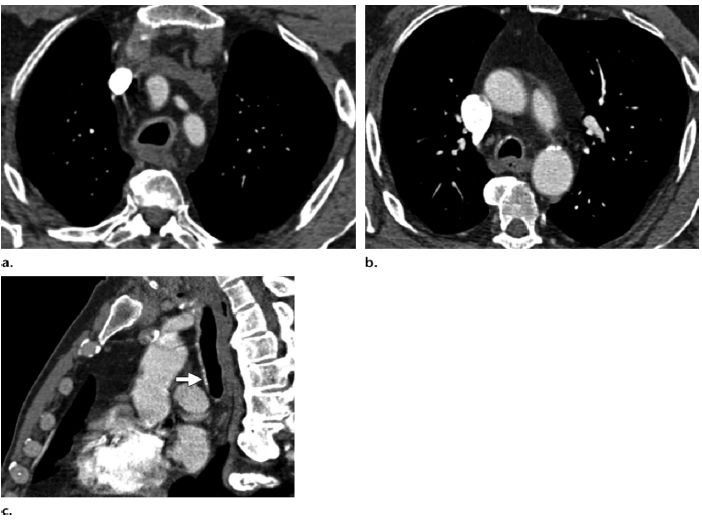

图 9 患者,女性,43岁,淀粉样变性累及气道,有进行性呼吸困难。胸部增强CT显示右肺上叶上气道起始部气管环状增厚(a)和(b)。(c,d)容积重建显示气管远端大段变窄